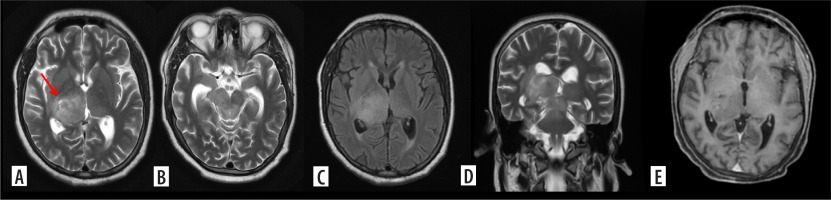

Figure 1

H3K27M mutant diffuse midline glioma. Axial T2, FLAIR and coronal T2WI images (A-D) show diffuse infiltrating midline tumour involving the right thalamus, medial aspect of left thalamus and extending into the midbrain. A few T2 dark areas (red arrow) are noted in the right thalamic region of the lesion, suggestive of high-grade tumour morphology. In the post-contrast study (E), the mass shows no enhancement, characteristic of midline diffuse glioma. This lesion was a histopathologically proven H3K27M mutant